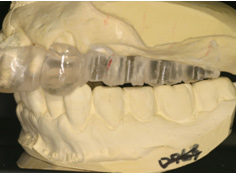

![]() |

診断用Wax up(ワックス・アップ)を基にX線撮影用ステントという、透明樹脂でできたマウスピースのような型をつくります。 |